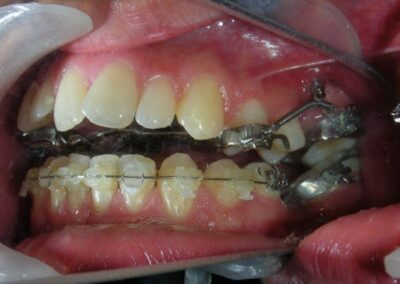

Was installed a Hyrax-type 10mm palatal expander of the Brazilian trademark Morelli® , modified by the author to be adapted to receive TADs microscrews, in order to initiate maxillary disjunction with MARPE (Mini-implant Assisted Rapid Palatal Expansion), TADS was installed with skeletal anchorage placed bilaterally having as references the roots of the maxillary canines and first premolars. Prior to insertion, local infiltrative anesthesia was administered using 2% lidocaine hydrochloride with 1:100,000 epinephrine. A total dose of approximately 0,8 mL per side (cortical infiltration technique). The TADs were inserted under aseptic conditions using a manual driver. Microscrew Evolution 1,6 Ø x 10 mm from the Argentine brand Odontit® . The Hyrax expander was then fitted and activated after 48 hrs .

Protocol of one activation per day was followed for a period of three weeks where the first clinical and radiographic evaluation was performed, showing clear signs of skeletal expansion, including the presence of a midline diastema. One more week of activations was added with a total of 28. The patient reported moderate headache during the first week of activation.

Having successfully achieved the expansion, we proceed to the intrusion of the posterior superior sectors, modifying the Hyrax by adding anchoring hooks at the buccal level of the first premolars. Using the Hyrax as anchorage, we sought a parallel intrusion. This could be replaced by a palatal bar. TADs were installed bilaterally at the mesial level of the first molars, inserting them as parallel as possible to the roots.